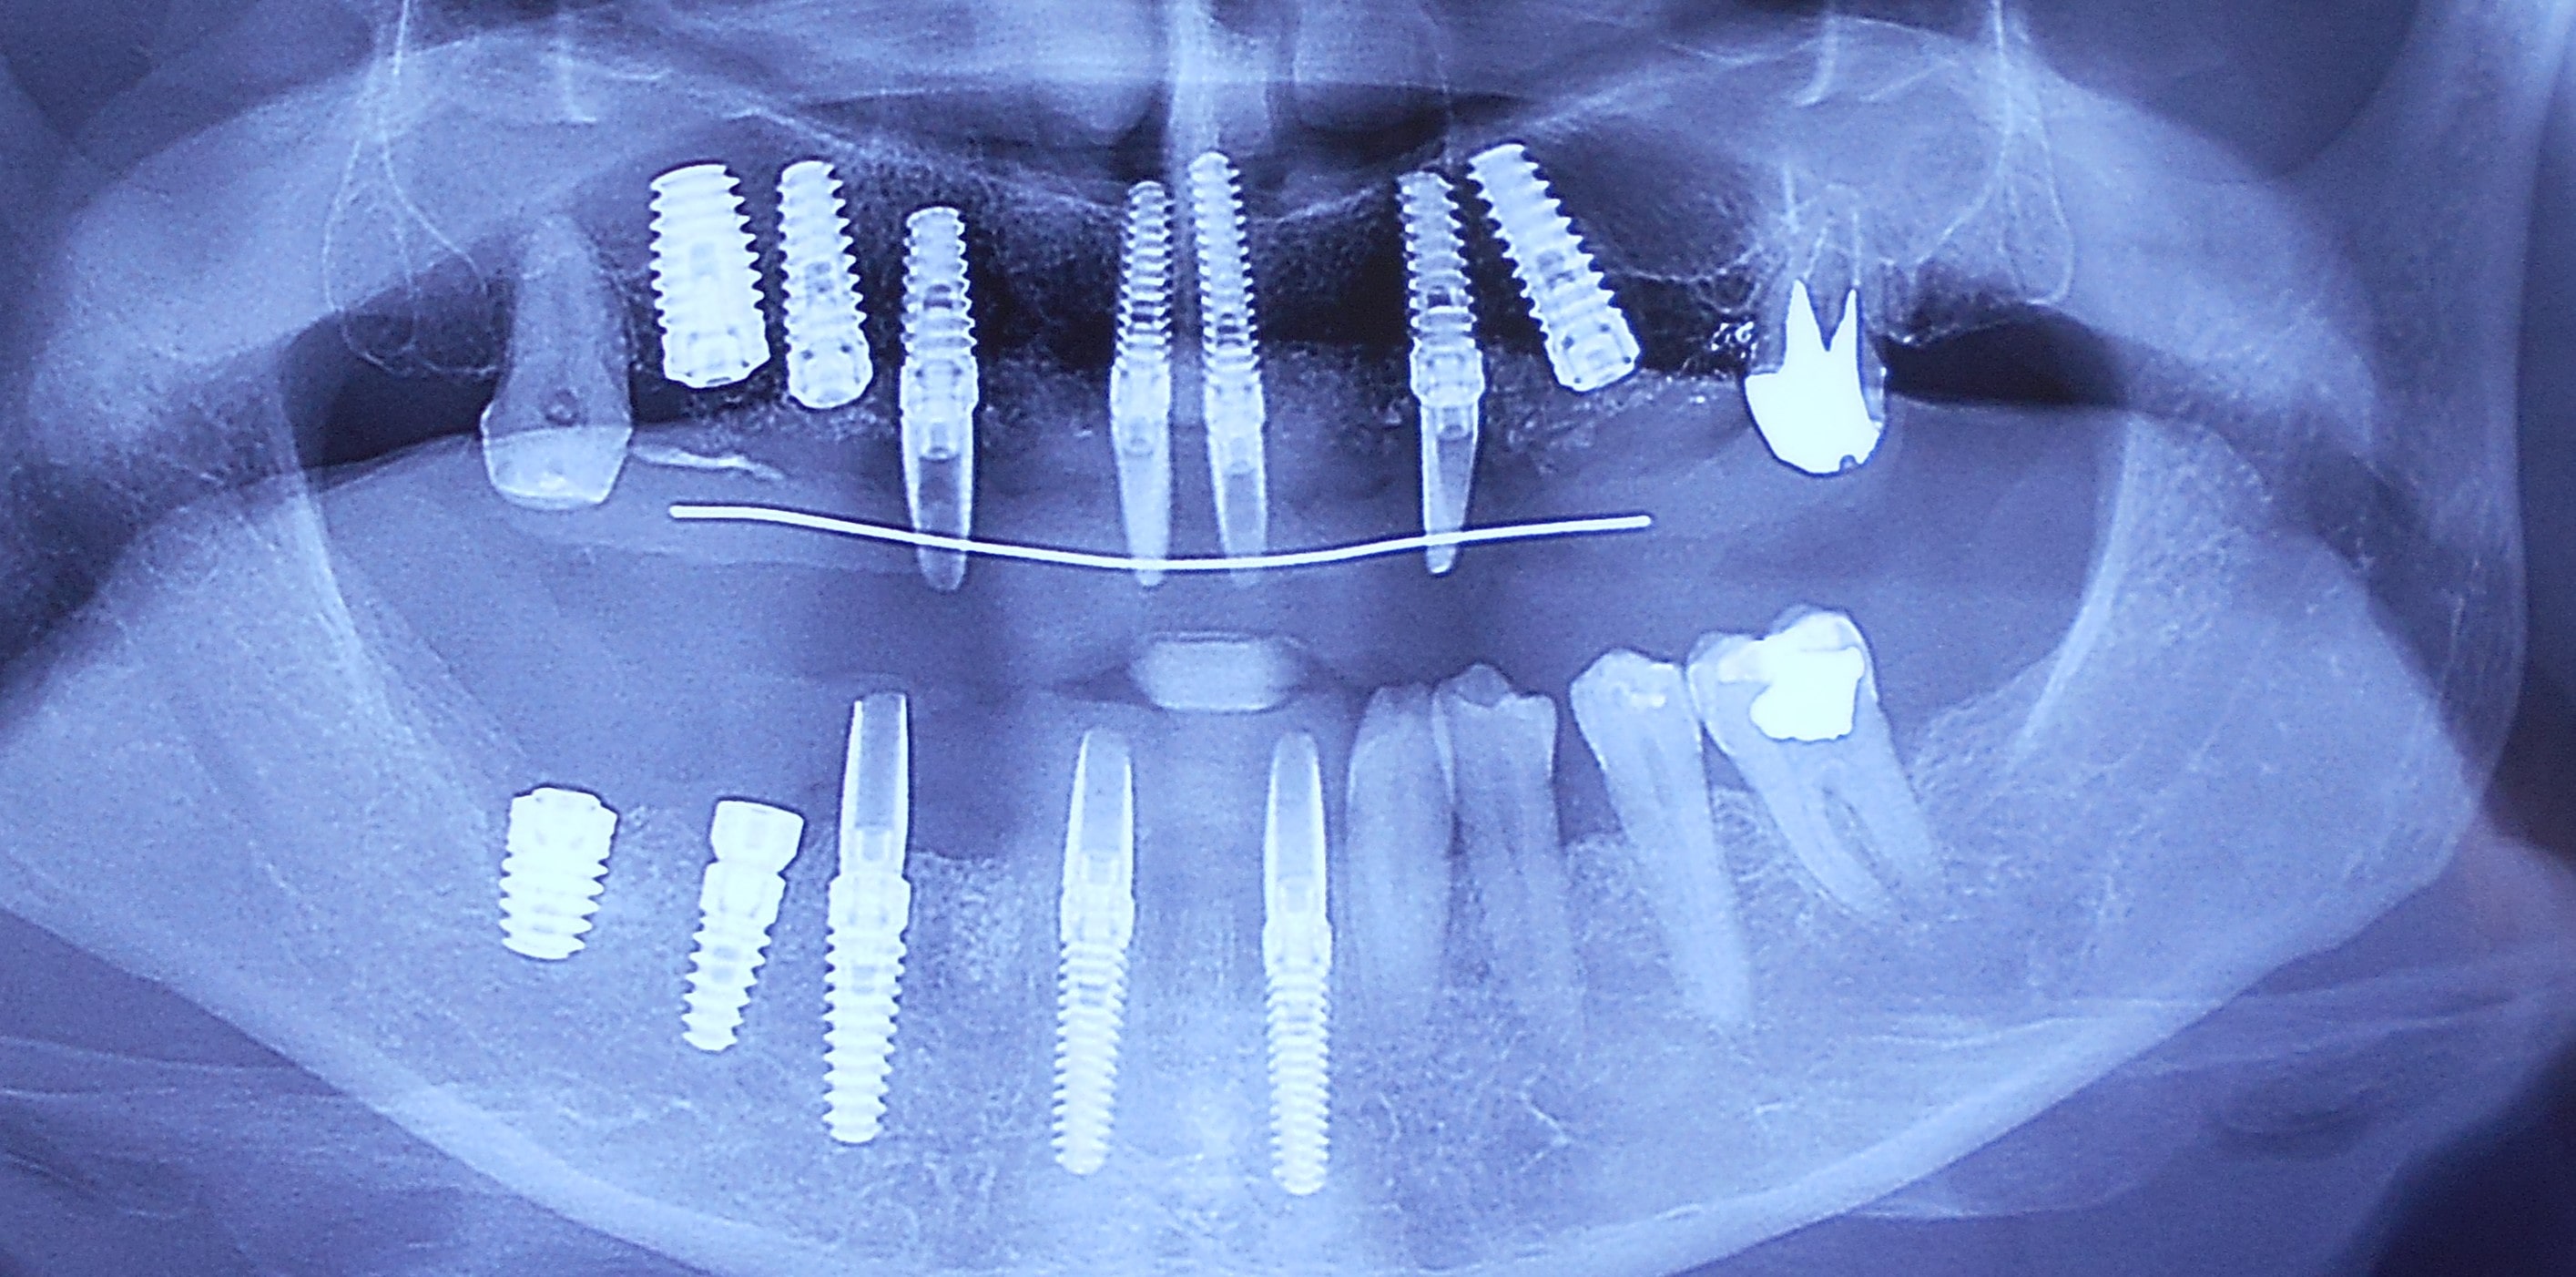

Pacijent iz Nemačke, kod koga smo estetsko i funkcionalno zbrinjavanje rešili cirkonijum keramičkim krunicama sa ugradnjom kratkih implantata u donjoj vilici zbog smanjene visine kosti, a u gornjoj vilici na levoj strani odmah nakon vađenja zuba je ugrađen standardni implantata na mesto izvađenog zuba i ugrađen je tuberopterigoidni implantat da se ne bi radila komplikovana sinus lift procedura koja bi produžila vreme završetka rada na godinu i više dana. Rad uspešno završen i pacijent nema nikakvih problema već pet godina.

Pacijent 2

Pacijent sa obe strane gornje vilice je bio bezub, sa minimalnom horizonatlnom i vertikalnom visinom kosti kao i sa spuštenim sinusom. Nakon dužeg traženja rešenja za svoj slučaj u drugim ordinacijama da bi izbegao komplikovanu sinus lift proceduru prihvatio je naš predlog da se ugrade po tri implantata sa obe strane gornje vilice od kojih su dva tuperopterigoidna implanta, koji su rešili problem spuštenog sinuasa sa minimalnom traumom prilikom ugradnje. Slučaj rađen pre četiri godine. Na poslednjoj kontroli izgleda besprekorno.

Pacijent 3

Pacijent dolazi sa starim mostovima i izraženom parodontopatijom u donjoj vilici. Urađeno je skidanje postojećih mostova i istovremena ekstrakcija svih parodontopatičhin zuba uz ugradnju sedam implantata u gornjoj vilici i pet implantata u donjoj vilici. Pacijent je nakon tri dana bio privremneo protetski zbrinut sa fiksnim privremeni krunicama koje su fiksirane na tek ugrađenim implantaima. Nakon četiri meseca je izrađen fiksni cirkonijum kermički- bezmetalni most u gornjoj i donjoj vilici. Rad uspešno završen pre tri godine.

Pacijent 4

Pacijent iz inostranstva doalzi sa totalnom protezom u gornjoj vilici i sa uznapredovalom parodontopatijom preostalih zuba u donjoj vilici. Pacijent navodi da su mu u inostranstvu rekli da je nemoguće u gornjoj vilici ugraditi implantate bez velikih hirurških zahvata koji podrazumevaju transplantaciju kosti sa udaljenih delova tela i sinus lift proceduru. U gronjoj vilici je bila minimalna količina kosti sa izraženo spuštenim sinusima i sa minimalno vretikalnom i horizontalnom visinom kosti. Naše rešenje se sastojalo u sledećem: ugradnja deset implantata u gornjoj vilici u raspoloživu kost sa ugrdnjom veće količine veštačke kosti, od deset ugrađenih implanta dva implantata su tuberopterigoidna koji su zamenili sinus lift proceduru. U gornjoj vilici smo se opredelili za ugradnju većeg broja implantata kako bi prilikom izrade fiksnog protetskog rada dobili ravnomeran prenos pritiska žvakanja na implantate. U donjoj vilici intervencija je bila istovremena i ona je podrzumevala vađenje svih preostalih zuba i ugradnju osam implantata. Kompletno zbrinjavanje koje obuhvata hiruršku i protetsku fazu je trajalo tri meseca, tokom kojih je pacijent u gornjoj vilici bio zbrinut sa privremenom totalnom protezom, a u donjoj vilici sa fiksnim privremenim zubima koji su bili fiksirani na tek ugrađenim implantatima. Definitivni protetski rad je uspešno završen sa cirkonijum keramičkim - bezmetalnim mostovim pre četiri godine.

Pacijent 5

Pacijent kod koga je rađena kombinacija rešavanja bezubih prostora sa ugradnjom implantata, a nakon tri meseca kompletno rešavanje sa cirkonijum keramičkim -bezmetalnim krunica i mostovima.